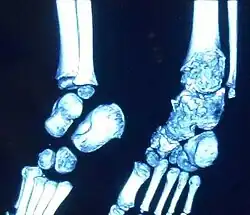

M. Trevor tritt einseitig zumeist an der unteren Extremität auf und führt im Laufe des Wachstums zur Fehlstellung und Deformierung des Gelenkes. Assoziation mit Enchondromatose ist beschrieben[3]. Der schmerzlose Überwuchs fällt im Kleinkindesalter auf, häufig an den Fußknochen, am Kniegelenk oder Sprunggelenk.

Die Diagnose kann im Röntgenbild gestellt werden aufgrund der typischen Lokalisation, des unregelmäßigen Überwuchses und des Auftretens von mehreren nicht miteinander verbundenen Knochenkernen, die an Epiphysen angelagert sind.[4] Eine Diagnosesicherung ist im MRT möglich.